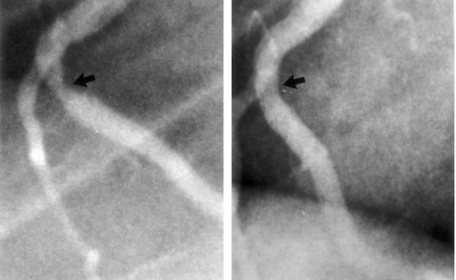

Heart disease is diagnosed via; EKG, Echocardiogram, Stress Test, Carotid & Intimal Thickness Test, CT Scan, Angiogram & Cardiac Catheterization.

Typical non-dimensional image

The data generated from these tests is presented numerically, using graphs or x-ray like images. RMHD moves beyond, numerical data / graphs and presents heart disease in a completely novel way. It will use the latest advancements in data visualization tools to create 3D graphic rich animations of the disease (eg. Computed Tomography Angiogram).

We can’t fix it, if we can’t see it.

My encounter with a killer. Sorry for image, but let’s put a face on this disease.